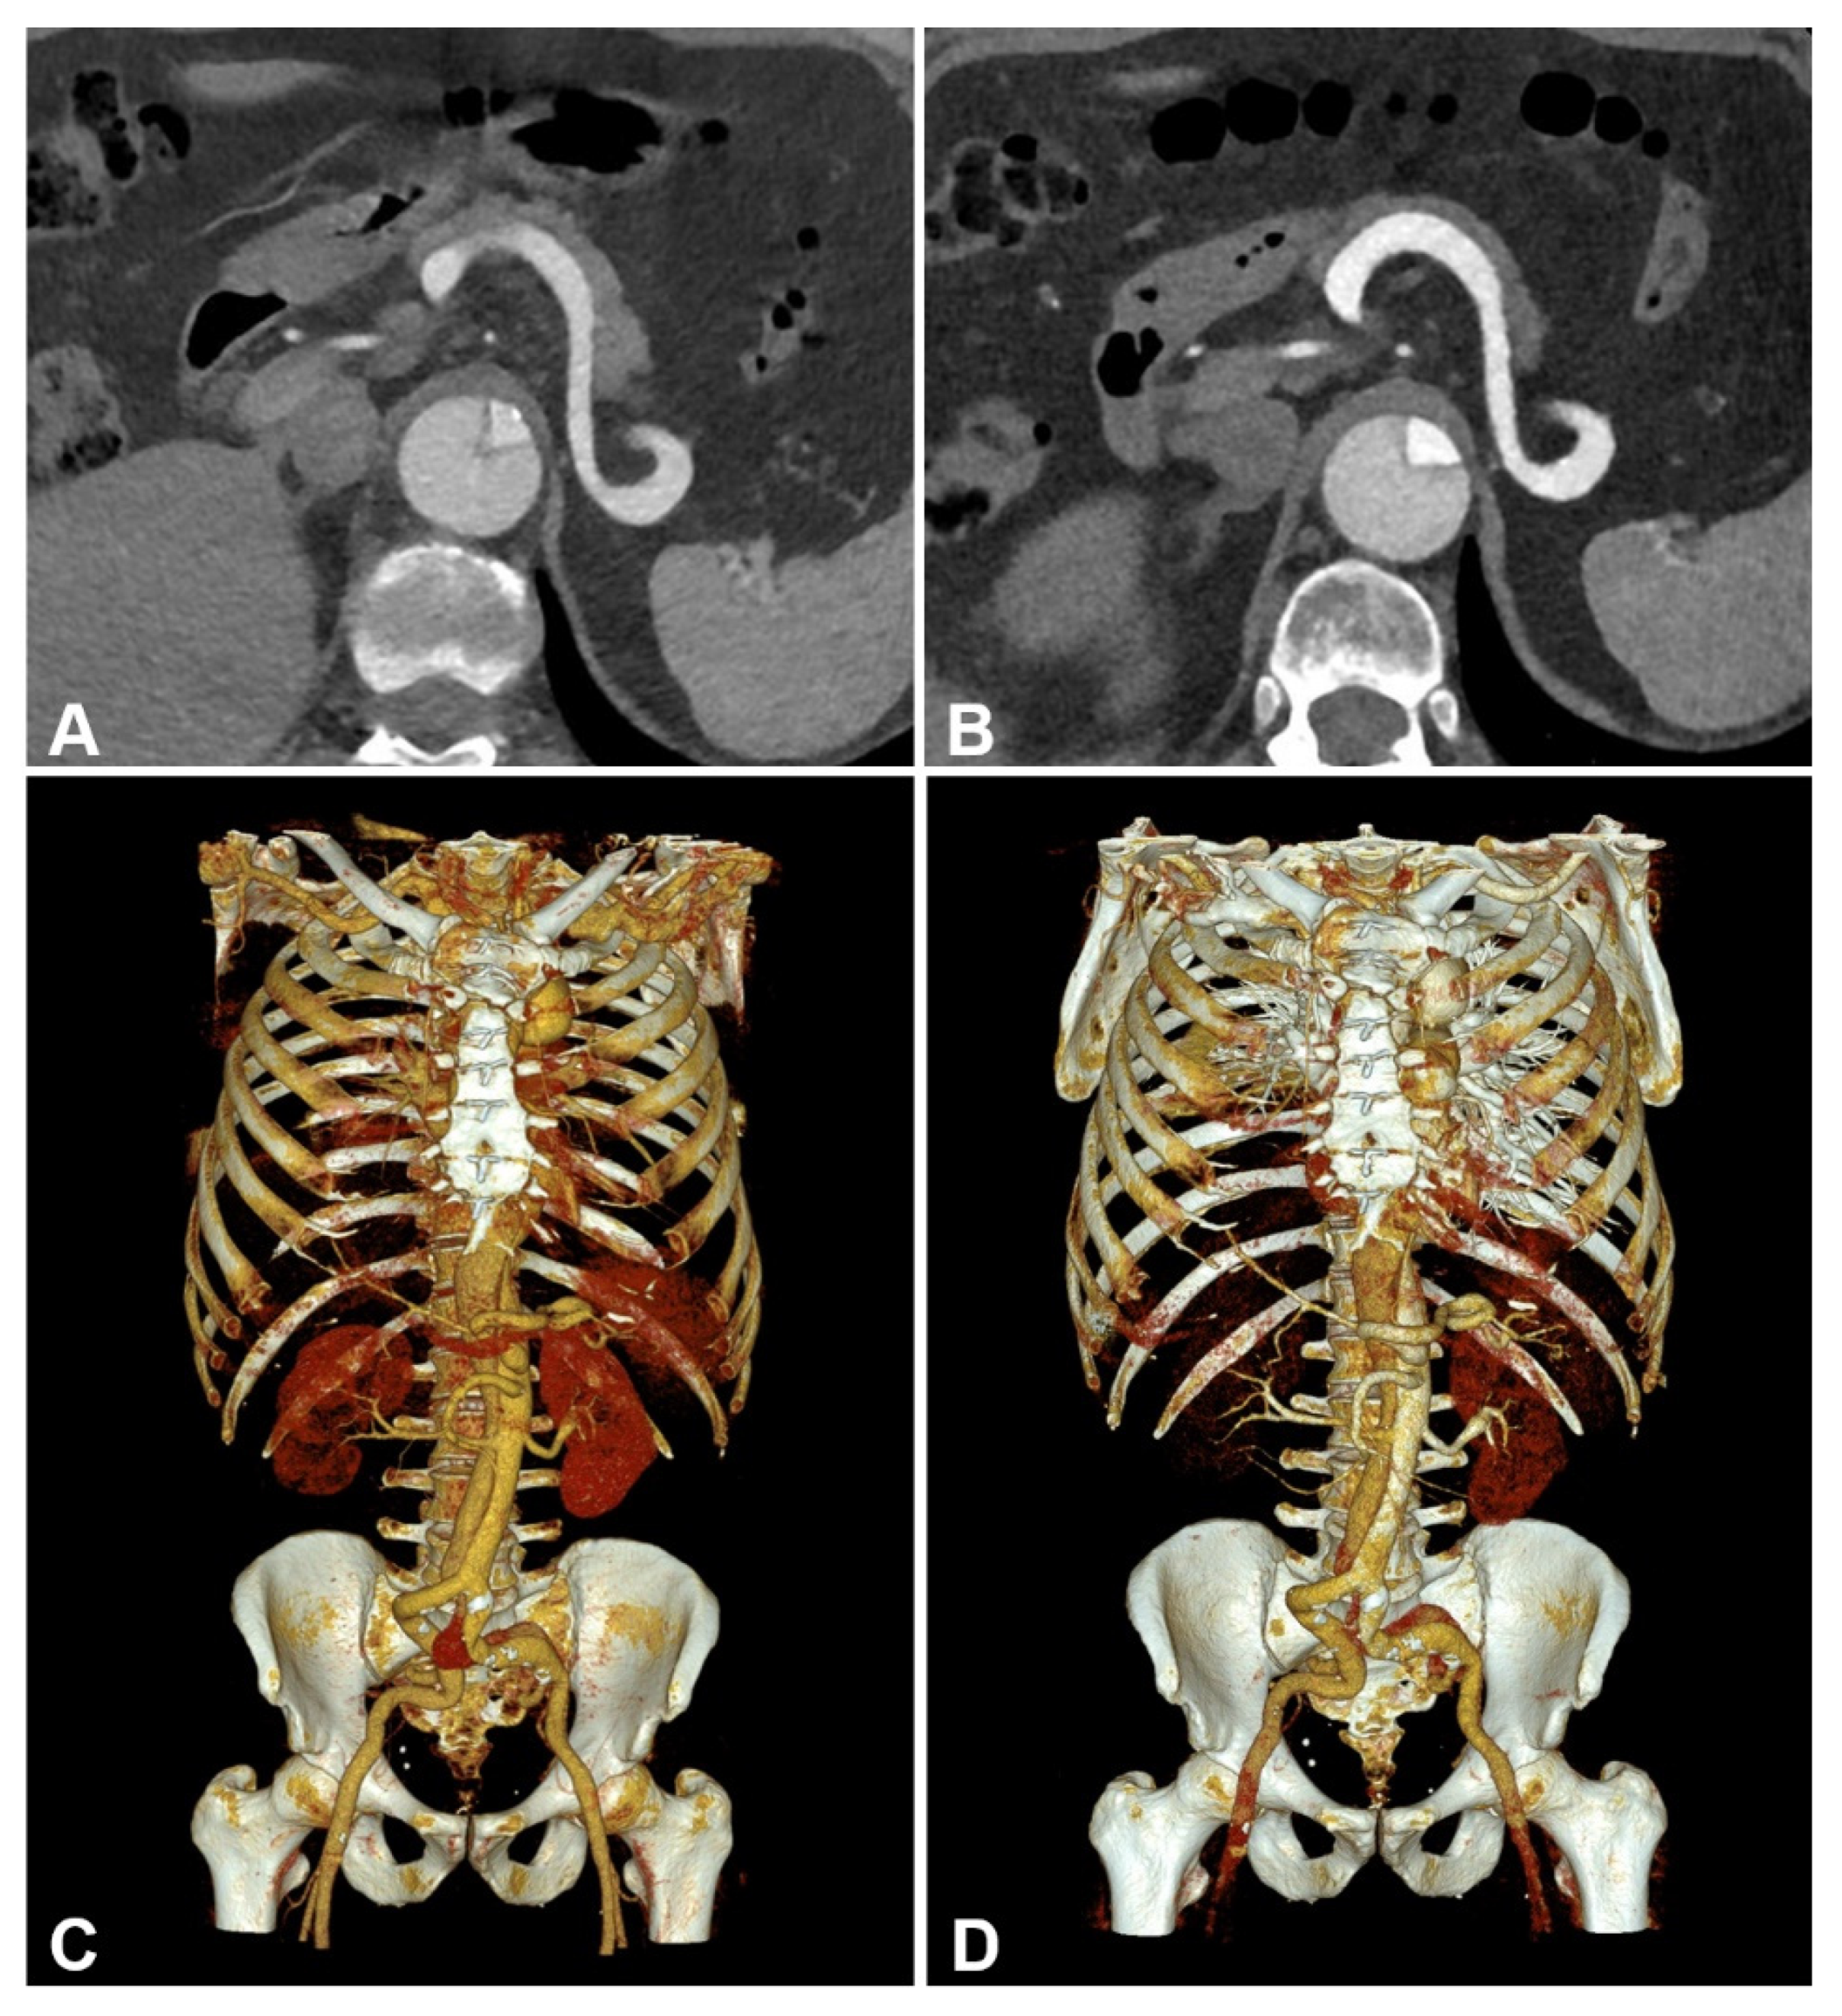

Figure 4.

Side-by-side comparison between energy-integrating-detector computed tomography (EID-CT) (A,C) and photon-counting-detector CT (PCD-CT) angiography (B,D) in a 61-year-old man with surgically repaired aortic dissection. EID-CT: CTDIVol 5.93 mGy; SSDE 6.52 mGy. PCD-CT: CTDIVol 4.58 mGy; SSDE 5.26 mGy. (A,B) representative axial orientated CTA images (reconstruction kernel Bv36; slice thickness/increment 3 mm; window setting: width 700 HU/center 100 HU) (C,D) cinematic volume rendering images.